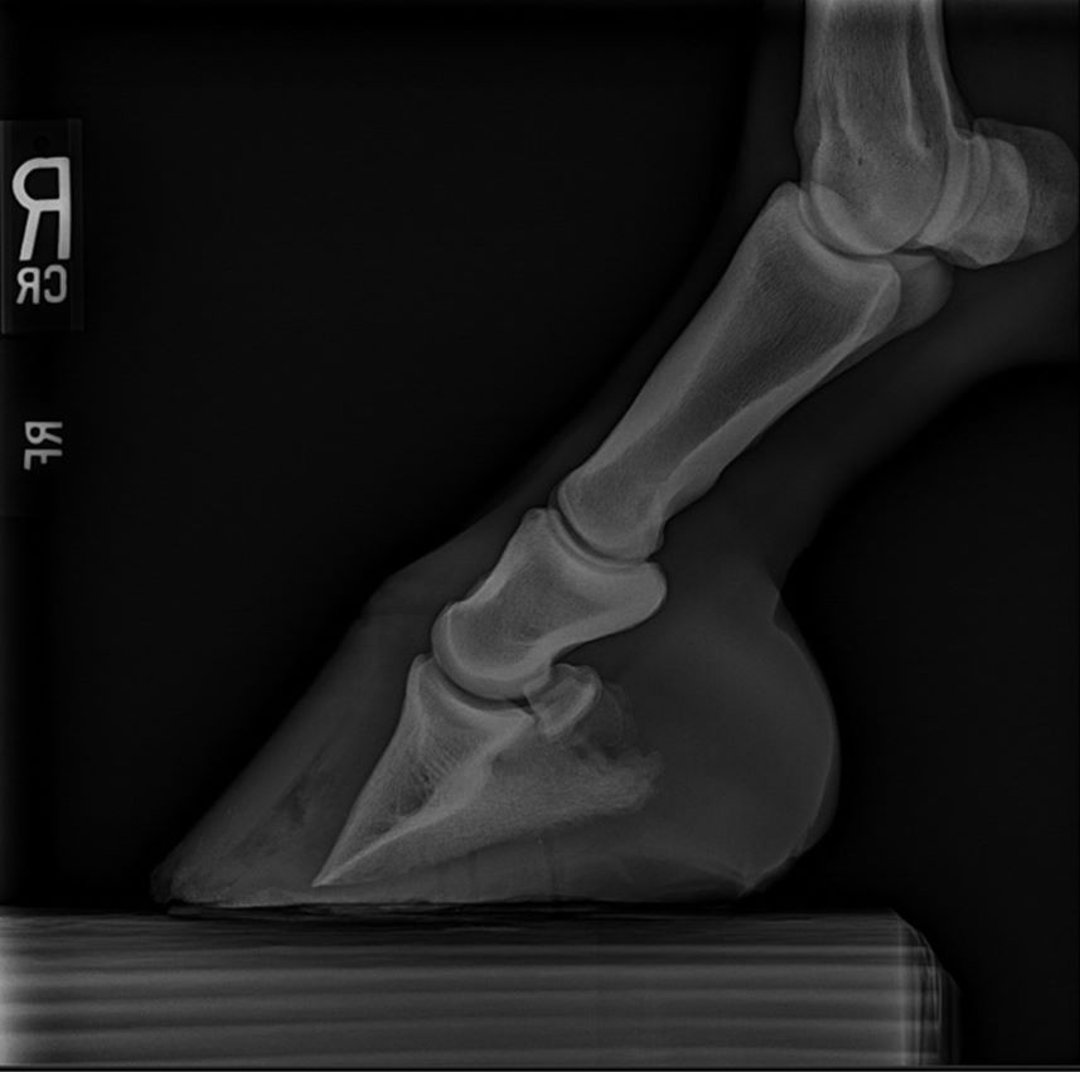

Laminitis in Horses Laminitis in Horses MSD Veterinary Manual Horse Coronary Band Swelling A condition newly recognized in horses is called coronary band dystrophy. Abdominal swelling due to fluid accumulation. The coronary band is the area at the top of the. • wounds below the coronary band cannot exhibit swelling, and do not undergo contraction; Horses are likely to sustain coronary band and hoof wall injuries at one time or another. Epithelialization occurs. Horse Coronary Band Swelling.